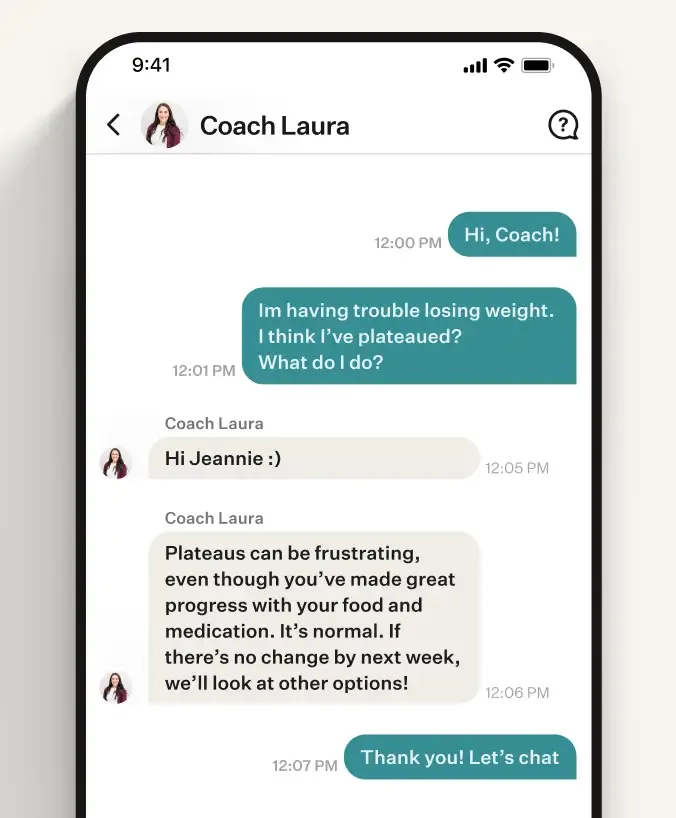

More than medication with Noom

Here's what real Noom users are saying:

Full access to Noom's program, focused on behavioral change and psychology for lasting results